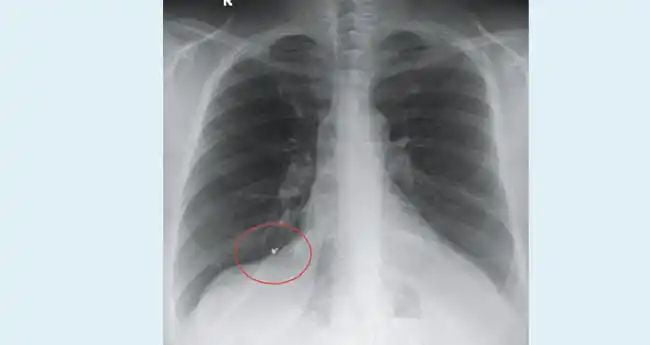

12 വർഷം മുമ്പ് കാണാതായ മൂക്കുത്തിയുടെ ഒരു ഭാഗം വീട്ടമ്മയുടെ ശ്വാസകോശത്തില് നിന്നു പുറത്തെടുത്തു. കൊല്ലം ശാസ്താംകോട്ട സ്വദേശിനിയായ നാല്പ്പത്തിനാലുകാരിയുടെ ശ്വാസകോശത്തില് നിന്നാണ് കൊച്ചി അമൃത ആശുപത്രിയിലെ ഇന്റർവൻഷണല് പള്മണോളജി വിഭാഗം മേധാവി ഡോ. ടിങ്കു ജോസഫിന്റെ നേതൃത്വത്തില് ശസ്ത്രക്രിയ കൂടാതെ ഒരു സെന്റിമീറ്റർ നീളമുള്ള ചങ്കിരി പുറത്തെടുത്തത്.

മൂക്കുത്തി കാണാതായ ദിവസം അതിന്റെ പ്രധാനഭാഗം വീട്ടില്നിന്ന് കിട്ടിയിരുന്നു. ചങ്കിരിക്കായി തെരച്ചില് നടത്തിയെങ്കിലും കണ്ടെത്താനായില്ല. ശ്വാസകോശത്തില് എന്തോ തറഞ്ഞിരിക്കുന്നതായി ശ്രദ്ധയില്പ്പെടുന്നത് കൊല്ലത്തെ സ്വകാര്യ ആശുപത്രിയില് കഴിഞ്ഞയാഴ്ച ശസ്ത്രക്രിയയ്ക്ക് വിധേയയായപ്പോള് നടത്തിയ സ്കാനിങ്ങിലാണ്. തുടർന്ന് കൊച്ചി അമൃത ആശുപത്രിയിലെത്തി നടത്തിയ പരിശോധനയില് ഇത് മൂക്കുത്തിയുടെ ഭാഗമാണെന്ന് കണ്ടെത്തുകയും പുറത്തെടുക്കുകയുമായിരുന്നു.